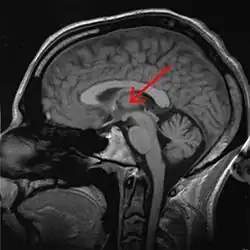

Thalamus

Thalamus (česky hrbol mezimozkový) je spolu s epithalamem součástí zadní části mezimozku (diencephalon) a je seskupením senzorických, asociačních a nespecifických jader. Zprostředkovává převod informací přicházejících z periférie do specifických projekčních a asociačních oblastí mozkové kůry a do důležitých center mozečku. Umožňuje také vzájemnou interakci vyšších oddílů CNS.